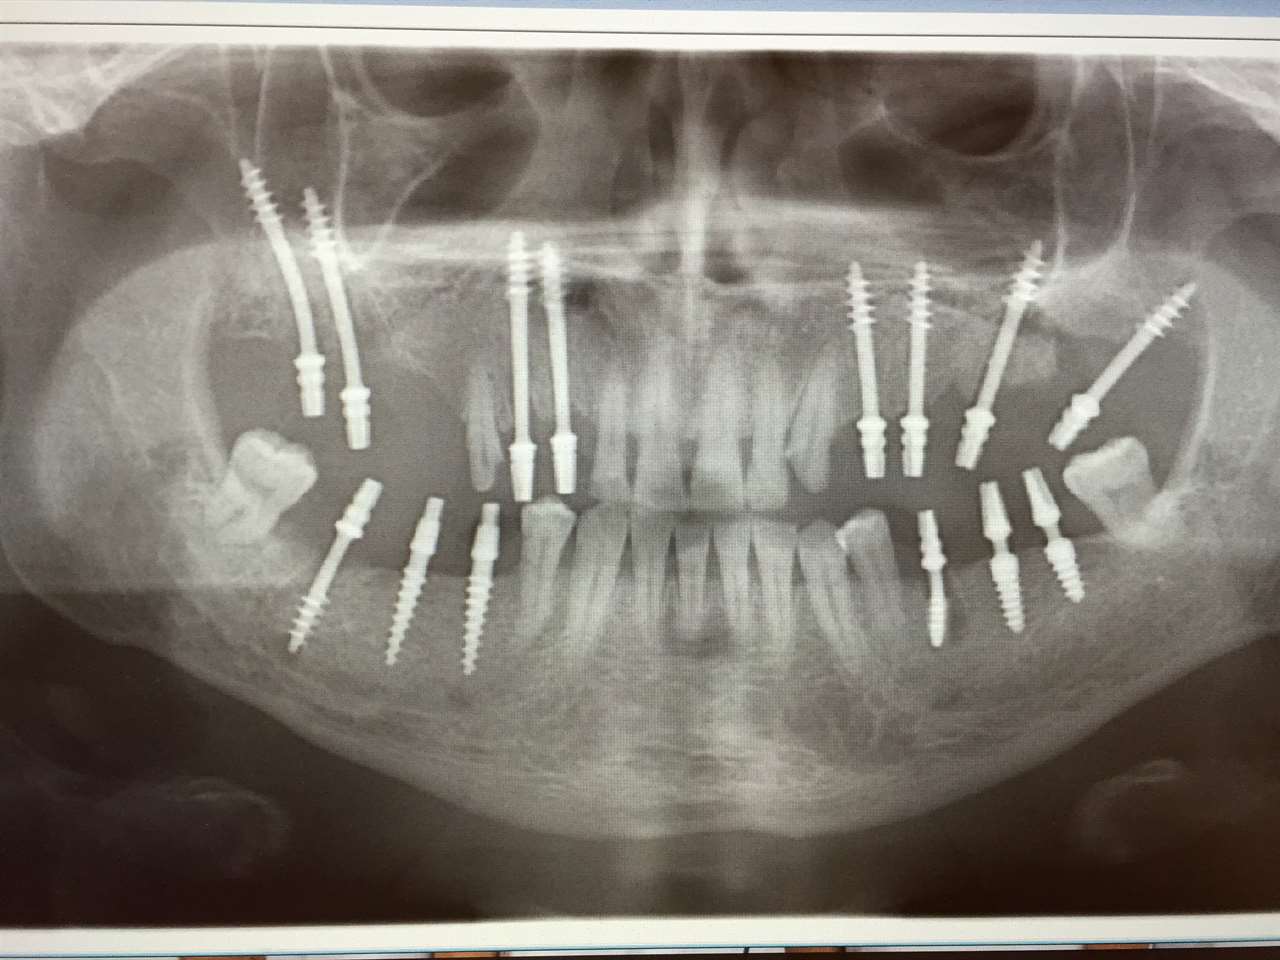

Elhanyagolt fogsor cseréje 2 nap alatt

2 nap alatt varázsoltuk ezt a szép esztétikus alsó, felső körhídat implantátumokkal megtámasztva a korábban elhanyagolt szájba. Az 1. nap 26 fogat távolítottunk el, mert annyira rossz állapotban voltak, és rögtön azonnal terhelhető IHDE svájci implantátumokat raktunk be, fentre 8, lentre 6 darabot. A sebeket összevarrtuk és intraorális szkennerrel digitális lenyomatot vettünk. 2 nap múlva pedig beragasztottuk a kész PMMA műanyag körhidakat. Dr. Kelemen Péter és a Symbion Fogtechnika munkája.